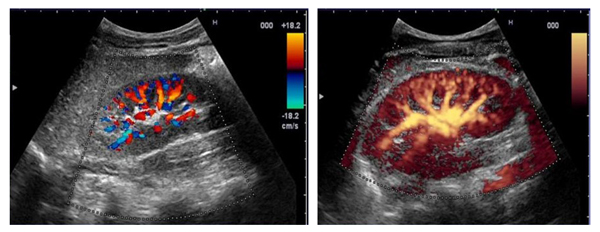

Исследование в режиме ЦДК (УЗИ сосудов почек)

В данном режиме врач проводит оценку состояния артерий и венозной сети, а также анализирует особенности кровотока.

Сначала специалист устанавливает датчик в области эпигастрия и находит устья почечной артерии. Правая почечная артерия находится ниже верхней брыжеечной артерии и может быть визуализирована по среднеключичной, передней и задней подмышечной линиям.

Левая почечная артерия расположена еще ниже правой. Ее структура и проходимость также оцениваются по передней и задней подмышечным линиям.

Кроме указанных артерий, врач также отслеживает мелкие кровеносные сосуды, находящиеся в корковом веществе почки.

Импульсная допплерография

Необходимо осознавать, что почки, подобно головному мозгу и сердцу, являются органами с высокой степенью кровоснабжения. Это означает, что на основе интенсивности кровообращения врач может создать так называемые доплеровские кривые. Эти кривые характеризуются выраженной диастолической составляющей и отсутствием обратного кровотока на протяжении всего сердечного цикла.

В процессе анализа специалист уделяет внимание максимальной скорости кровотока в систолу, конечной скорости в диастолу и промежуточным значениям между этими показателями. Кроме того, врач вычисляет время, необходимое для достижения максимальной скорости кровотока в систолу, а также период его ускорения.